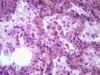

Подскажите как назвать данную пневмонию. По закону парных случаев, на данный момент у меня два разных случая с одинаковой морфологией. В морфологии в альвеолах эозинофильное содержимое, слущенные альвеолоциты, гигантские, многоядерные клетки, выраженный геморрагический компонент, местами немного лейкоцитов, свертки фибрина. Обширные свертки в бронхах. Очень похоже на вирусную, но как ее может назвать морфолог?

Интерстициально-десквамативная.

+ местами похоже на гиалиновые мембраны и в капиллярах межальвеолярных перегородок встречаются мегакариоциты.